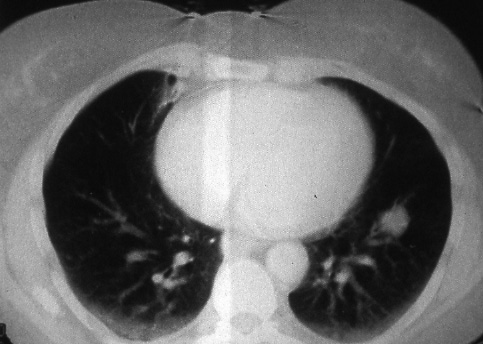

Fig. 34b:

Computed tomographic scan of the lesion in Fig. 34a, T1 N0 M0. The lymph nodes were not involved.